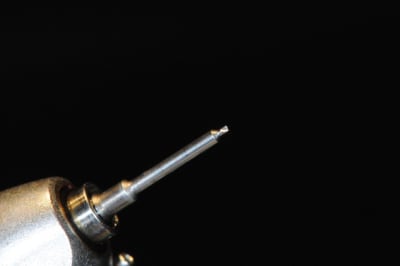

photo

1: foret de perçage pour que l'os puisse apporter du sang.

(initialement, c'est un foret pour les pins densply)

2-3: je fais des petits trous (comme Serge)

4: la boite avec toutes les vis (différentes tailles)

5-6: le foret de mise en place des vis et le foret destiné à faire un pré-perçage

7-8: et voilà 3 vis qui vont maintenir ma membrane au dessus de l'os.